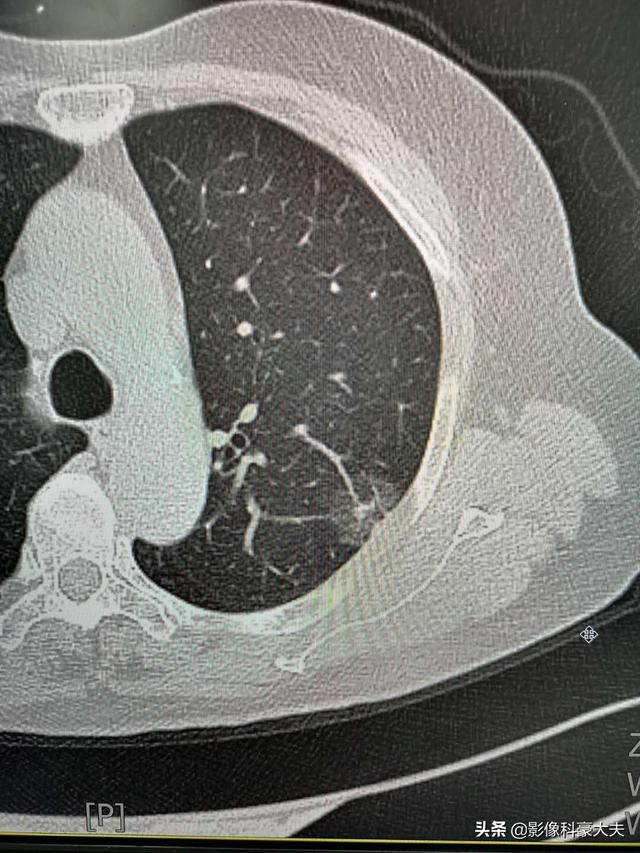

この老人も比較的幸運なことに、胸のつかえ、咳、微熱のために検査を受けた結果、左側に早期の肺腺がんが見つかった。

この初期の腺がんは治癒可能で、5年生存率は100%に近い。

発見が間に合ったから、進行がんになることはなかった。